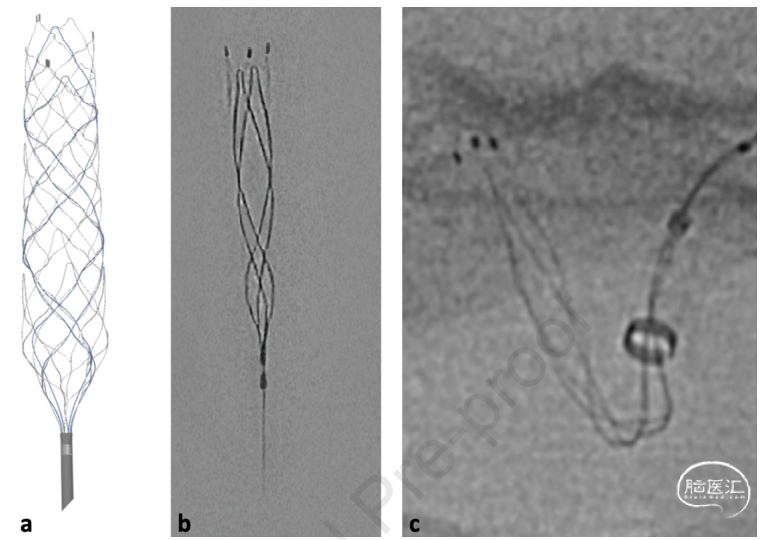

Aperio®复合取栓装置(APH;Acandis,Pforzheim,德国)是最近推出的一种完全不透射线的支架取栓装置,其开闭环复合设计包括用于加强贴壁性的较小闭孔和用于捕获和结合血栓的较大开孔。初步研究表明该设备具有合理的安全性和有效性。9-11新型 APERIO Hybrid17取栓装置 (AP17) 代表了对现有 APH 的进一步改进,采用低剖面结构,使其与 0.017 英寸微导管兼容。AP17被批准用于 1.0-4.0 mm的血管直径,而传统 APH 的血管直径为 1.5-5.5 mm。这些技术进步可能有助于对中段或远端血管闭塞进行血管内治疗,这是传统取栓支架难以处理的问题。德国科隆大学附属医院神经外科中心的Lukas Goertz等人通过一项多中心回顾性研究,分享了他们使用新型低剖面 APERIO Hybrid17支架取栓装置 (AP17) 治疗急性缺血性卒中近端和远端血管闭塞的初步经验。结果发表在2022年8月的World Neurosurgery。

图1. APH取栓装置:a. APH取栓器;b. DFT线不透线完全性使器械的完整长度可见;c. APH用于M1取栓的图像。